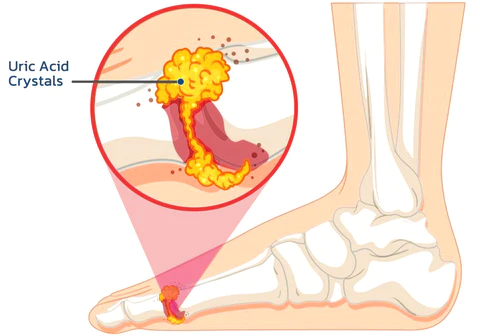

Gout (metabolic arthritis) is caused by an increase in glancing biosynthesis, excessive production of uric acid, or poor excretion of uric acid, resulting in an increase in uric acid in the blood and thus causing gout, which is characterized by hyperuricemia and recurrent episodes of gouty acute arthritis, commonly occurring in the joints of the big toe but also in the hands, knees, elbows, etc.